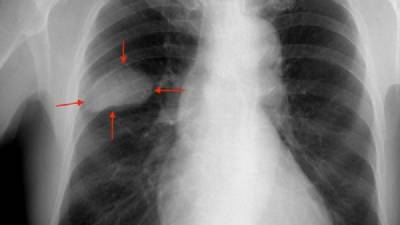

Lung cancer is notoriously difficult to raise money for research for – campaigns and charity events for cancer investigation funds do not attract much response for lung cancer since the general public view is that sufferers 'had the choice not to take up smoking' and that it is 'self-inflicted', although Spain's main cancer organisation AECC says this is not always the case and non-smoking lung cancer patients worry about stigma.

Research is happening, but slowly – although a potential breakthrough was presented at the recent European Society of Medical Oncology (ESMO) annual conference, with two types of treatment that may be able to substitute chemotherapy in advanced non-microcytic lung cancer, increasing survival rates.

Specialist in the field at Madrid's Ramón y Cajal University Hospital Dr Pilar Garrido says the first study, titled FLAURA, shows that the latest-generation medication Osimertinib – taken orally – not only slows down the progression of the disease, but increases survival rates and is far less toxic than chemotherapy.

It is used in patients with Epidermic Growth Factor Receptor (EGFR) mutations and who represent around 10% to 15% of the total.

The second study, Dr Garrido announced – titled CHECKMATE 227 – involves a medication that can be used instead of chemotherapy for patients whose cancer does not have any identifiable targets for direct, focused treatment.

She stresses that neither drug cures lung cancer, but they increase the 'therapeutic storage' in the body and prolong life without depleting quality of life – the patient will not be feeling ill all the time in exchange for living longer, as is often the case with chemotherapy in incurable (chronic, but controllable) or terminal cancer.